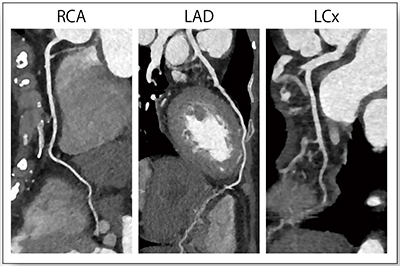

●時間分解能

SOMATOM Driveの75msという高い時間分解能は,心臓撮影において非常に威力を発揮する。症例2は,虚血性心疾患疑いの症例であるが,心拍数が100bpmほどであっても,拍動の影響が非常に少ない画像を得ることができている(図2)。

図2 症例2:虚血性心疾患疑い(56歳,女性,HR:100bpm)